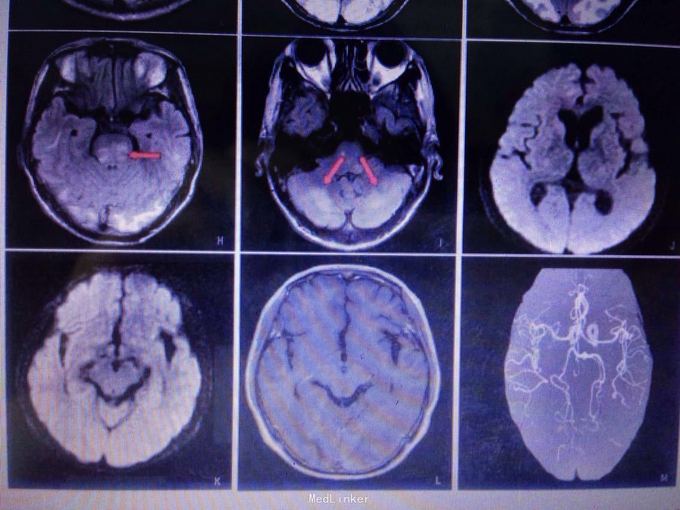

查体可见血压升高,昏睡,双眼视力眼前光感,眼球水平运动受限,视物重影,肌力约3-4级。 头颅CT见双侧枕叶皮层下对称低密度灶。 MR提示双侧枕叶下长T1对称病灶,flair相为高信号。腰穿脑脊液未见明显异常。

患者经治疗意识状态逐渐恢复,复查颅脑MR提示原有病灶较前明显减少。考虑患者可逆性后部脑病综合征诊断较为明确。